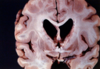

What clinical symptoms are most compatible with the disease process seen in the picture?

a) Dementia, social disinhibition

b) Memory loss, language deficits, visuospatial impairment

c) Acute course of hypersalivation, hydrophobia, encephalopathy & death

d) Writhing fluid movements, ataxia, psychosis

e) Parkinsonism, hallucinations, neuroleptic sensitivity

Caudate Atrophy

seen in Huntington’s Disease

d) Writhing fluid movements, ataxia, psychosis